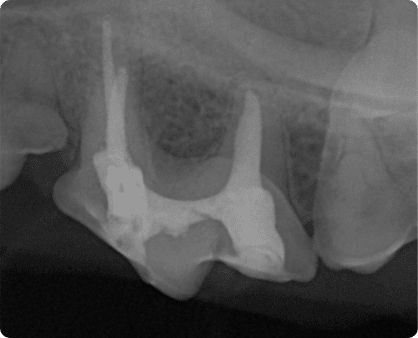

육안으로는 확인이 어려운 잇몸 아래, 치아 뿌리 및 턱뼈의 병변을

치과 방사선으로 진단

치아파절로 인해 신경이 노출되었거나,

감염으로 인한 치수염이 있을 경우 필요한 치료